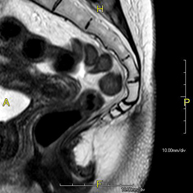

RM de Sacre-còccixProva diagnòstica no invasiva que consisteix en l'obtenció d'imatges d'alta definició anatòmica del sacre i còccix mitjançant l'ús d'un camp electromagnètic i ones de ràdio (amb un emissor i un receptor). No utilitza radiació ionitzant. Indicacions: dolor sacrococcigi i traumatisme.